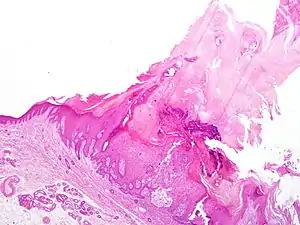

Cutaneous horn usually arises due to an underlying epidermal lesion, the most common being verruca vulgaris (wart), actinic keratosis (a potentially pre-malignant lesion of dysplastic keratinocytes), or squamous cell carcinoma (a form of skin cancer). These can look essentially identical clinically. The only reliable way to diagnose which type of lesion is present under the horn is to biopsy the lesion and have it microscopically examined by a pathologist (or dermatologist).